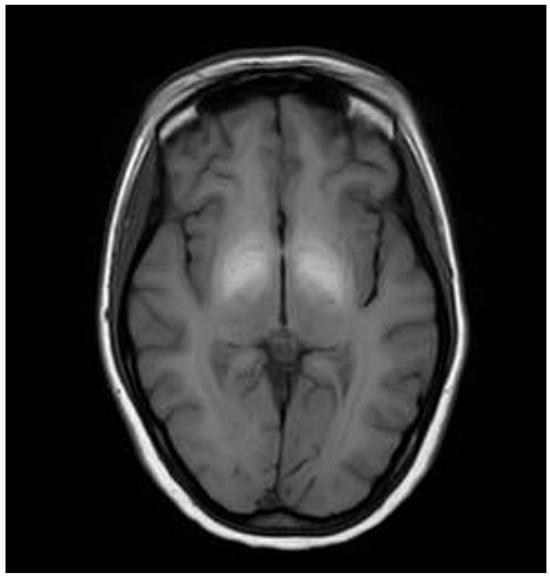

3.1. Classical Brain MRI Examination in WD Patients

| Atrophy (assessed on T1 sequences) | |||

| Cortical | 0 | 1 | 2 |

| Central | 0 | 1 | 2 |

| Midbrain | 0 | 1 | 2 |

| Cerebellar | 0 | 1 | 2 |